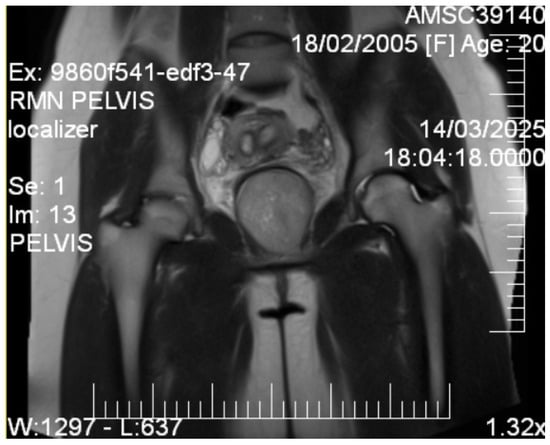

Given the patient’s young age and solid mass characteristics raising concern about malignancy, comprehensive magnetic resonance imaging (MRI) was performed using a 1.5-Tesla scanner with multiplanar sequences (General Electric, Cluj-Napoca, Romania). The MRI demonstrated signal intensity patterns highly suggestive of leiomyoma: isointense to muscle on T1-weighted imaging, markedly hypointense on T2-weighted imaging (characteristic of leiomyoma due to high fibrous content), restricted diffusion with high ADC values of 0.9 × 10−3 mm2/s (b-values: 0, 1000 s/mm2) consistent with benign leiomyoma, and homogeneous enhancement following gadolinium administration. In the literature [12], benign leiomyomas typically demonstrate ADC values in the range of 0.8–1.2 × 10−3 mm2/s, atypical leiomyomas may overlap, but are often slightly lower (0.7–1.0 × 10−3 mm2/s), while leiomyosarcomas tend to show more pronounced restriction, often <0.8 × 10−3 mm2/s. These ranges overlap, highlighting that although MRI provides highly suggestive features, histopathological confirmation remains essential. MRI also confirmed the septate uterus and showed detailed anatomical relationships (Figure 3 and Figure 4).

Figure 3.

Coronal T2-weighted pelvic MRI. The image shows a well-circumscribed, T2-hypointense solid mass located in the vesicovaginal space (6.9 cm), displacing adjacent pelvic anatomy. The bladder is displaced anteriorly, the vagina posteriorly, while the rectum and bowel are visualized further posteriorly. Gluteal and pelvic floor musculature are partially delineated laterally. These features are consistent with a leiomyoma.